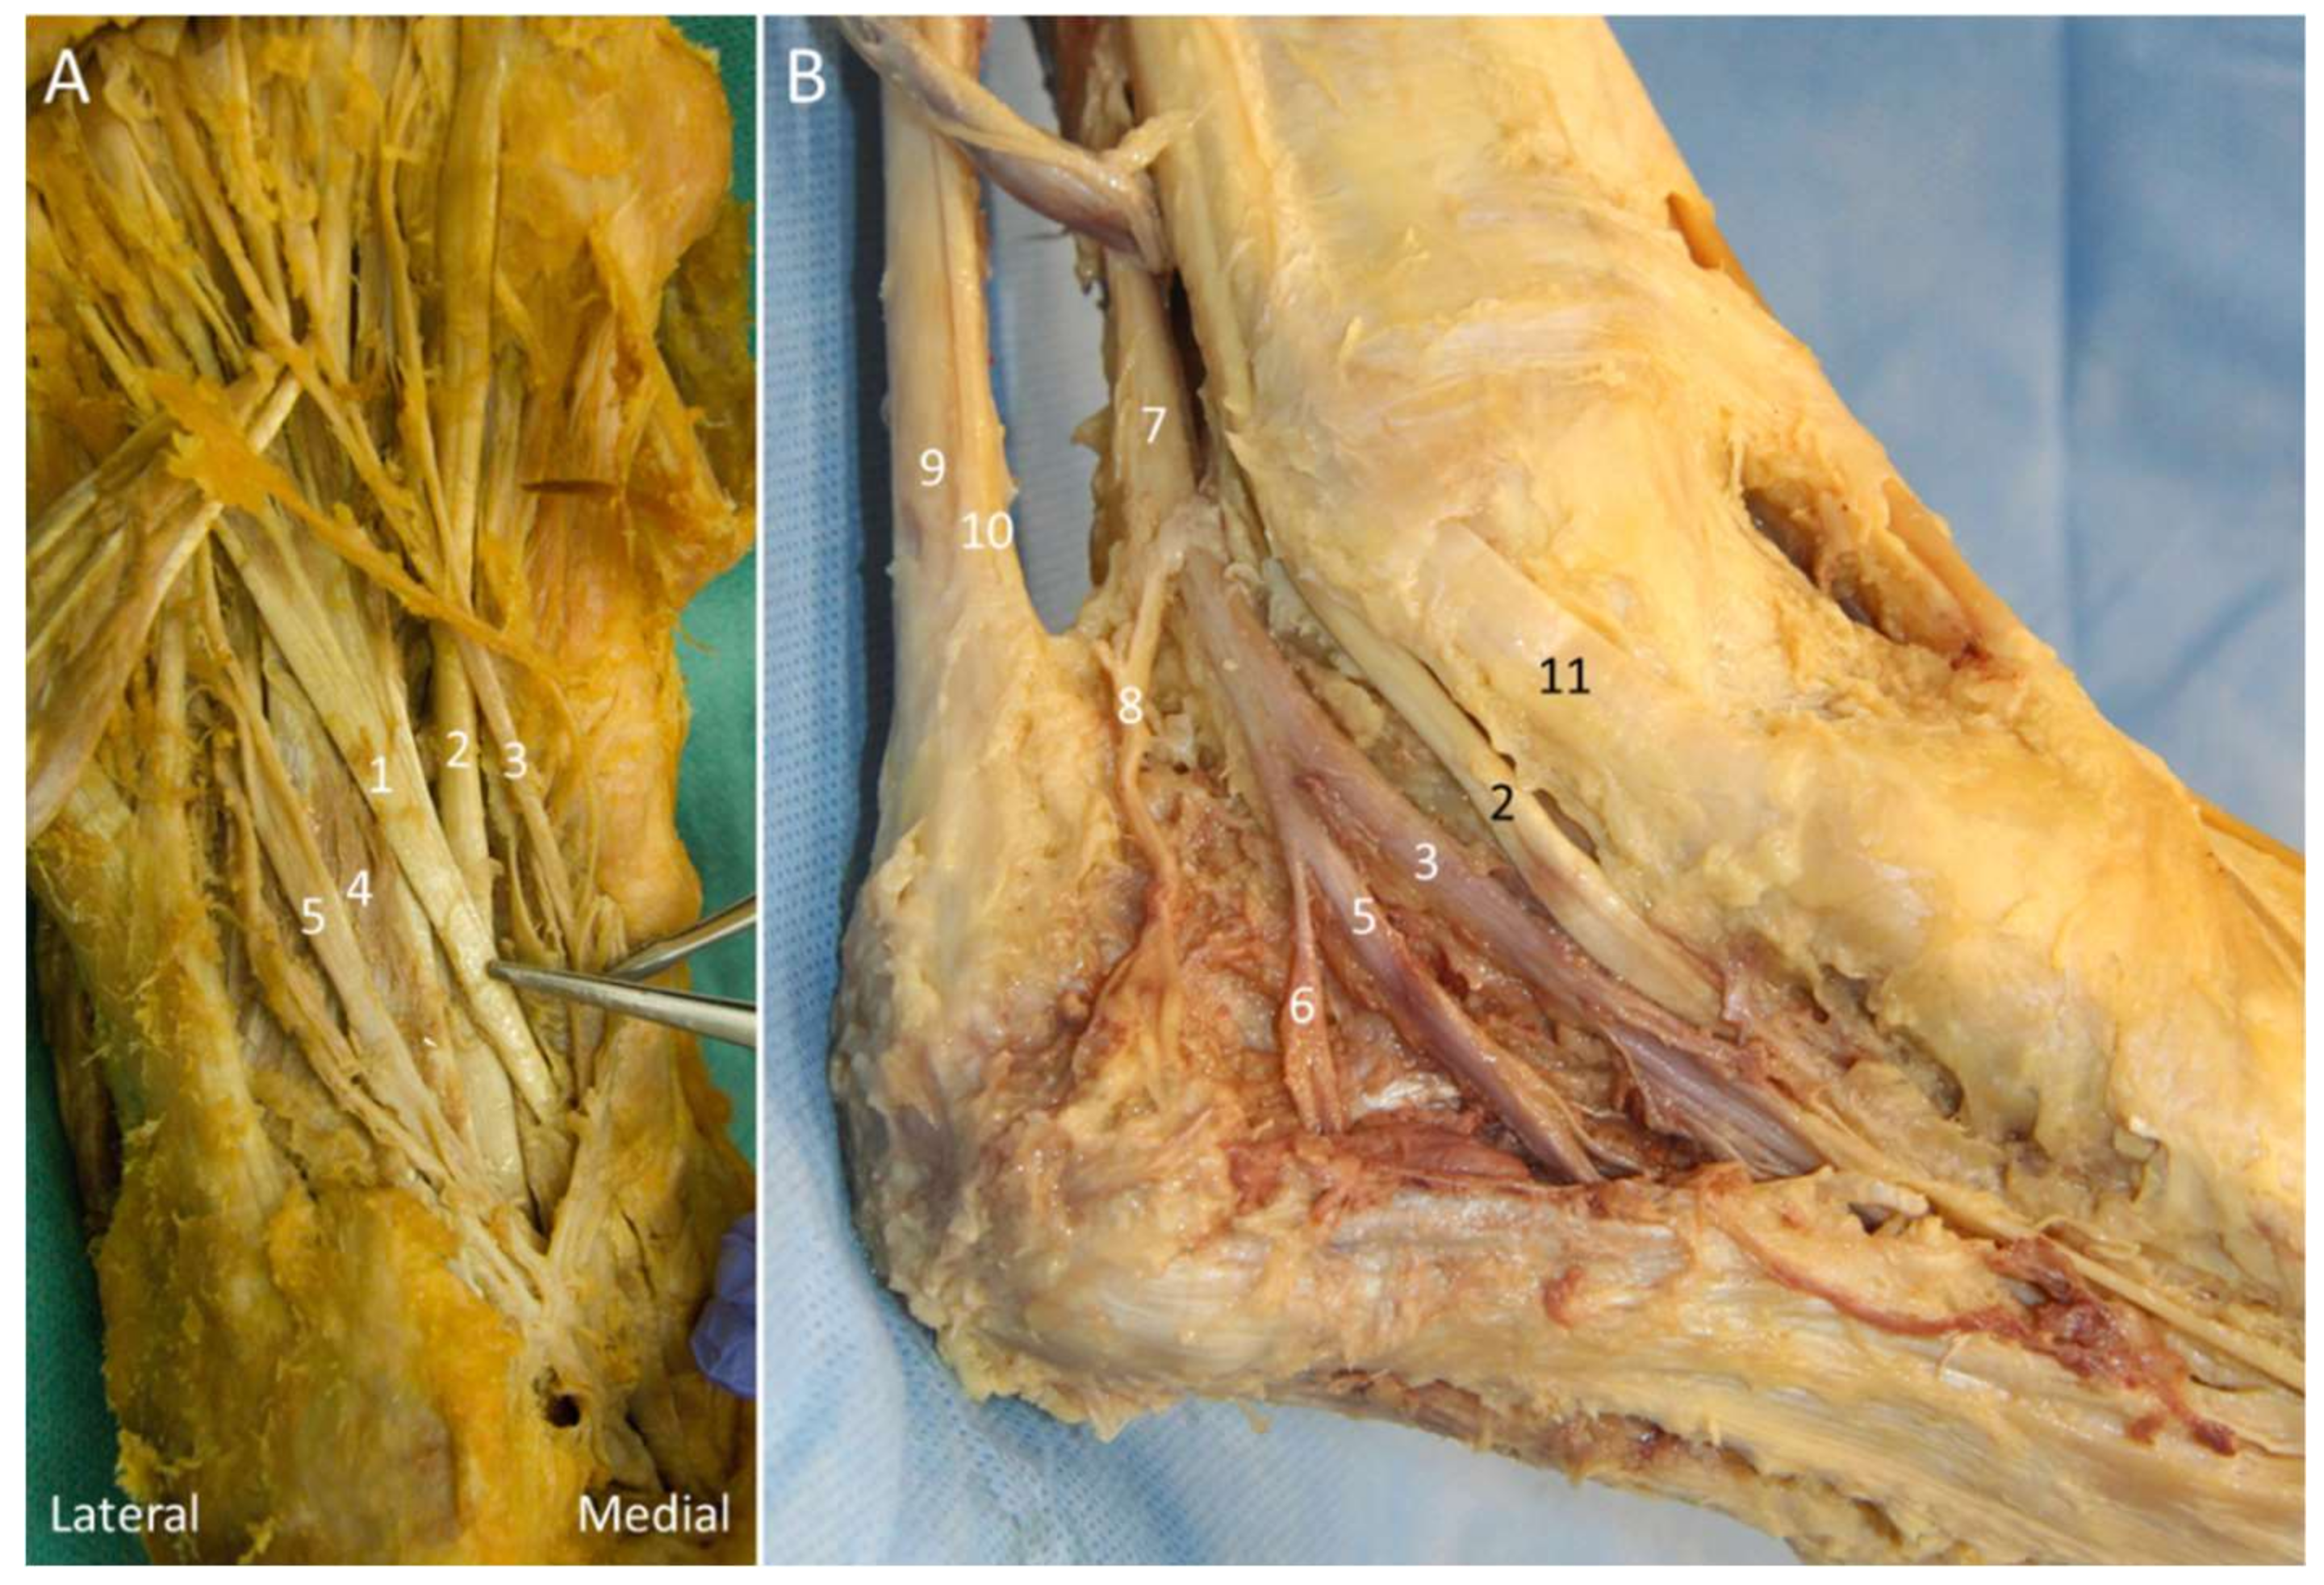

5.2. Baxter Nerve

5.2.1. Anatomy

5.2.2. Scanning Technique

5.2.3. Clinical Relevance